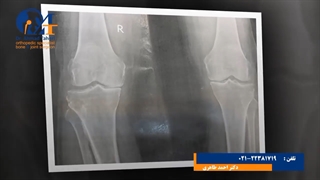

تعویض مفصل زانو توسط دکتر منصور ابوالقاسمیان-برای اطلاعات بیشتر به آدرس سایت دکتر منصور ابوالقاسمیان متخصص ارتوپدی و فوق تخصص جراحی لگن و زانو http://drabolghasemian.com/ مراجعه کرده یا با شماره تماس 02188703402 , 09338216202 تماس بگیرید